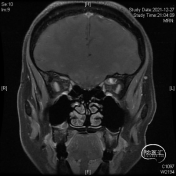

研究表明此入路除细小的滋养血管外无其他重要结构!皮肤切口选择近眶缘眉弓美容切口,紧贴眶上壁分离骨膜,保护眶筋膜,病变紧贴眶上壁,导航下确定眶尖紧贴眶上壁的病变,外观呈浅紫兰色,考虑既往有出血所致,显露肿瘤!

球后眶尖部位及海绵窦区的病变因为位置深在,周围重要结构众多,对神经外科医生具有极高的挑战性。神经内镜技术发展给我们提供了一条思路。我们通过相关解剖研究发现,病变位于海绵窦外侧壁、颈内动脉外侧、颞极内侧,可选择经眶外侧壁入路;病变位于眶尖内侧,累及海绵窦侧壁,经眶内侧壁入路更为适合;病变主体位于鞍区向一侧海绵窦侧壁侵袭,可以考虑内镜经鼻入路。眶内上壁病变,因为无重要结构,经眶入路最适合!